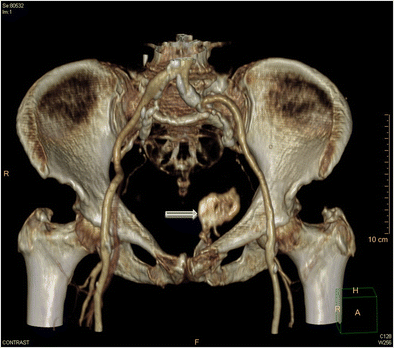

Importance Of Both Internal And External Iliac Artery Interrogation In Pelvic Trauma As Evidenced By Hemorrhage From Bilateral Corona Mortis With Unilateral Aberrant Origin Off The External Iliac Artery